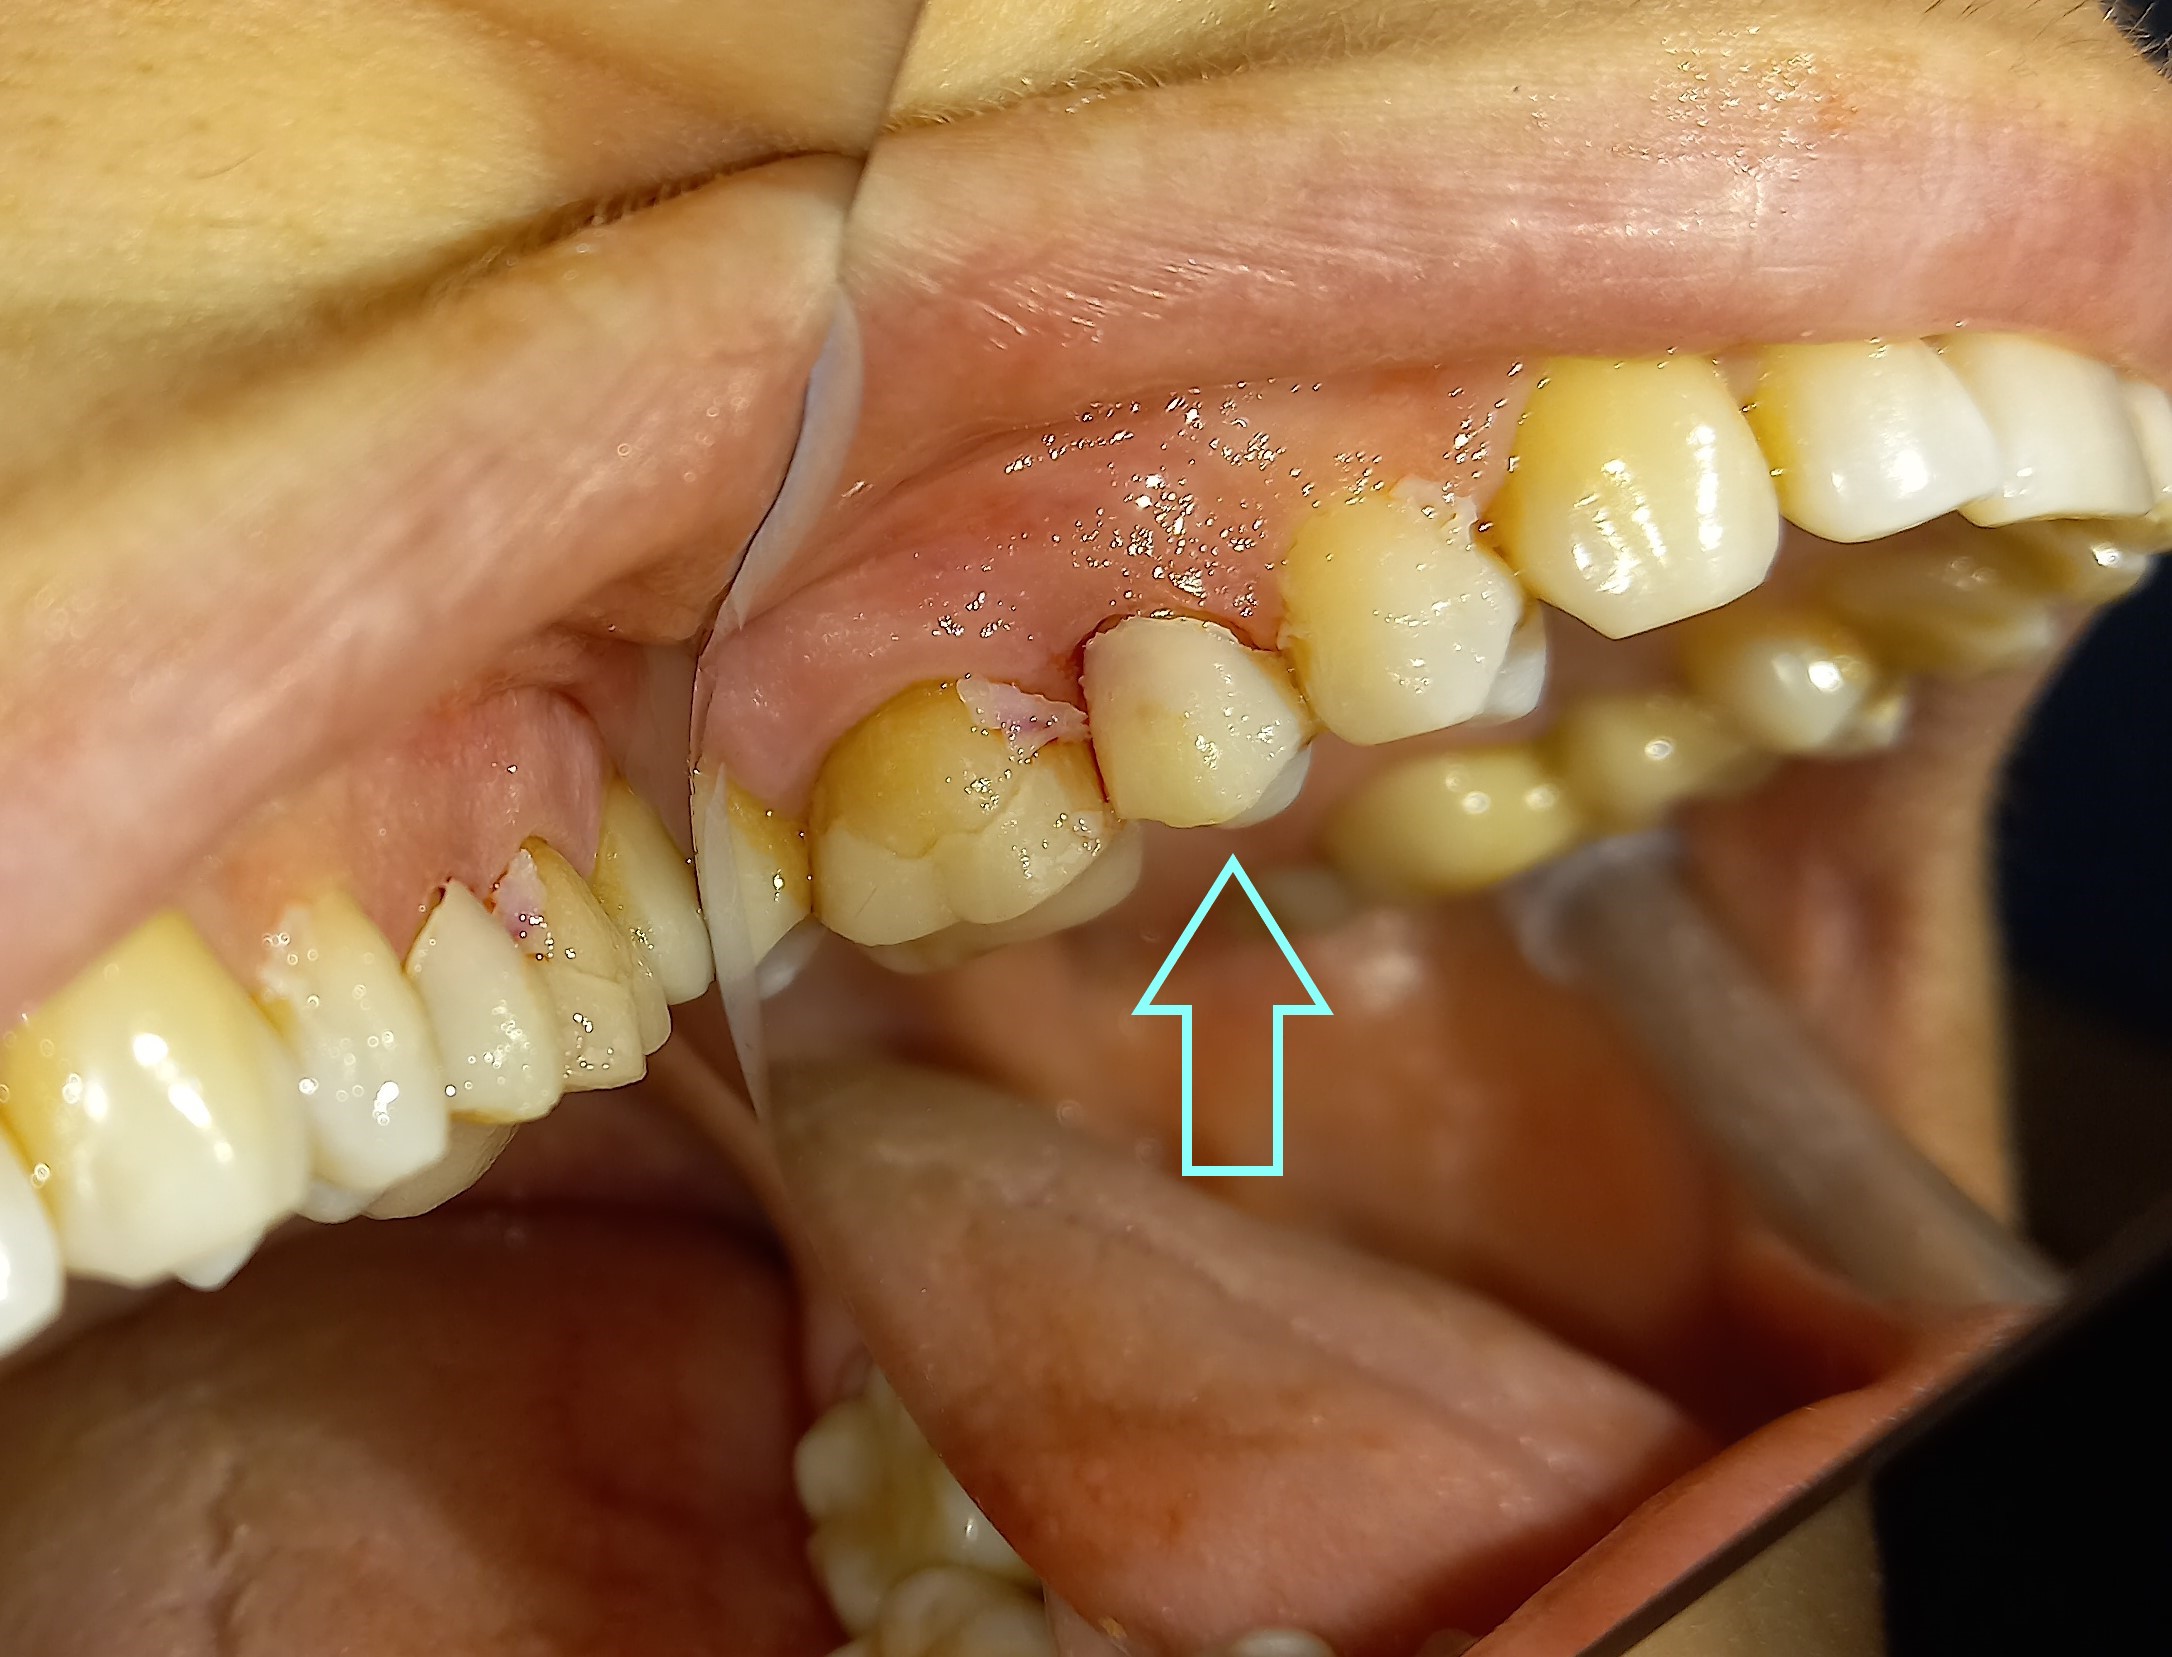

Ο πρώτος γόμφιος στην αριστερή πλευρά της κάτω γνάθου είχε απονευρωθεί στο παρελθόν. Ο ασθενής δεν θέλησε να καλύψει το δόντι με θήκη, ώστε να είναι πλήρως προστατευμένο με αποτέλεσμα το δόντι να σπάσει (όπως φαίνεται στην αρχική εικόνα). Η λύση θεραπείας ήταν η κατασκευή στεφάνης δοντιού, αφού προηγουμένως το δόντι τροχίστηκε καταλλήλως και ο οδοντοτεχνίτης κατασκεύασε την ολοκεραμική θήκη ζιρκονίου.

Το δόντι είναι πλέον πλήρως προστατευμένο και μπορεί να αντέξει στο πέρασμα των χρόνων.

ΠΡΙΝ

ΜΕΤΑ